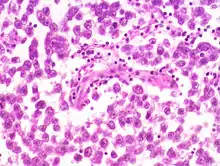

- Семинома (около 38%). Инвазивная злокачественная опухоль, построенная из герминогенного атипичного эпителия. Встречается наиболее часто, довольно рано даёт метастазы. Нередко сопровождается некрозами.[5] Поражает всё яичко, оставляя свободным только узкое кольцо нормальной ткани между опухолью и белочной оболочкой.[6]